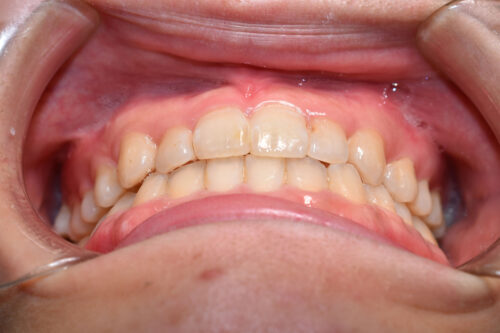

初診時年齢 28歳 女性

歯のでこぼこ(叢生)

下顎右側第一大臼歯欠損(歯をぬいた)

を主訴に

池袋よりひとつ隣駅の東京都豊島区大塚駅すぐの大塚たまみ矯正歯科へ

いらっしゃいました。

歯のがたつき (叢生)

と

受け口が認められました。

2026年(令和8年) 8月 JR巣鴨駅徒歩3分の場所へ 移転予定の

本症例も

下顎右側第一大臼歯欠損

上下とも歯が唇側に傾斜し

下の歯が上の歯よりも外にでている 受け口の状態でした。